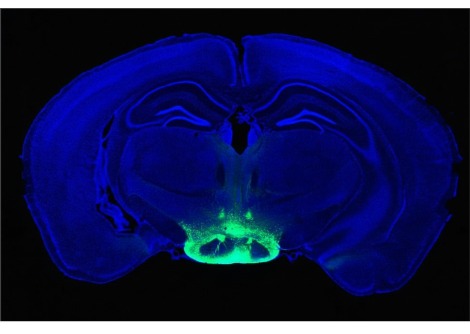

يقوم الانزعاج من لدغة البعوض أو رد الفعل التحسسي بتنشيط الخلايا العصبية الحساسة للحكة في الحبل الشوكي. يقول الباحثون في الدراسة التي تمّ نشرها في الثامن عشر من آب من عام 2017 في دوريّة "علوم" Science أنّ هذه الخلايا العصبية "تتواصل" مع بنية بالقرب من قاعدة الدماغ تسمى "نواة الفقرة العضديّة" parabrachial nucleus وهي منطقة معروفة بتلقي معلومات عن الأحاسيس الأخرى مثل الألم والتذوق.

يُقرّب هذا الاكتشاف الباحثين خطوة أخرى نحو معرفة المكان الذي تنتهي به إشارات الحكّة. يقول المؤلف المشارك في الدراسة "يان-غانغ صن" وهو عالم الأعصاب في الأكاديمية الصينية للعلوم في شنغهاي: "إنّ هذه النواة هي مركز التتابع الأول ل [إشارات الحكة] القادمة للدماغ".

تشير البحوث السابقة إلى أنّ هناك شبكة من الخلايا العصبية في الحبل الشوكي تتشابك فيها إشارات الحكة. أظهرت الخلايا العصبية في العمود الفقري والتي تقوم بإنتاج بروتين يُطلق عليه غاسترين والذي يقوم بإفراز مستقبل الببتيد أنّها مهمة في إرسال إشارات الحكة. لم ترتبط هذه الخلايا العصبية مباشرة بنواة الفقرة العضديّة PBN. وجد فريق صن بدلاً من ذلك أنّها "تتحدّث" مع الخلايا العصبية الأخرى التي ترسل رسائل إلى نواة الفقرة العضديّة .

وجد صن وزملاؤه أنّ القوارض قد أظهرت عند إعطائها حقن من العقار الذي يُحفّز الحكة التحسسية نشاطا أكبر في تلك الخلايا العصبية التي تربط الحبل الشوكي بنواة الفقرة العضديّة. قام الباحثون بجعل الخلايا العصبية الواصلة إلى نواة الفقرة العضديّة حساسة للضوء في تجربة أخرى، ثم قاموا باستخدام ضوء لوقف تلك الخلايا العصبية من إرسال الرسائل. أظهرت الفئران التي تمّ إعطاؤها دواء حكة أثار حكّة أقل عندما تم تعطيل تلك الخلايا العصبية.